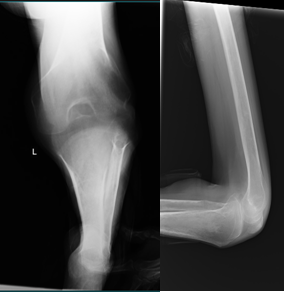

On general examination, the patient was thin built, with normal higher functions. Systemic examination was normal except a small non- tender, freely mobile granuloma in his right breast. He was walking with the help of two crutches and right lower limb, keeping his left lower limb hanging in air due to deformities. Examination of musculo-skeletal system revealed normal spine, normal upper limbs and normal right lower limb. On the left lower limb, he had 30 degrees fixed flexion deformity (further movement from 30 to 90 degree) and 10 degrees abduction deformity (further abduction from 10 to 30) at left hip, with restricted rotations which could not be assessed due to abnormal position of the limb. The left knee had 110 degrees flexion deformity with further flexion up to 160 degrees. The left ankle was in 30 degrees fixed plantar flexion deformity and all the toes also had plantar flexion deformity. Sensation in the limb was normal and power normal in the muscles. There were three firm, mildly tender, granulomatous swellings of size 2cm.x4cm., in subcutaneous location, one each in left lower thigh, left upper calf and at the left heel. Adductors of left hip, iliotibial tract, hamstring muscles and gastro soleus muscles were found tight and contracted. X- ray of the knee (Figure 1) and pelvis did not reveal any gross bony abnormality except the flexed position, though proper x-rays could not be done due to extreme flexion at knee. CT scan or MRI of knee also could not be done due to the abnormal positioning of the limb. The patient did not agree initially for FNAC (Fine Needle Aspiration Cytology) from the swellings. All blood parameters were found within normal limits, including tests for HIV after counselling.

Figure 1 Anteroposterior and lateral view of left knee. Ap view shows foreshortened leg due to extreme deformity. Lateral view shows 100 degrees flexion deformity at knee without any bony or soft tissue abnormality.